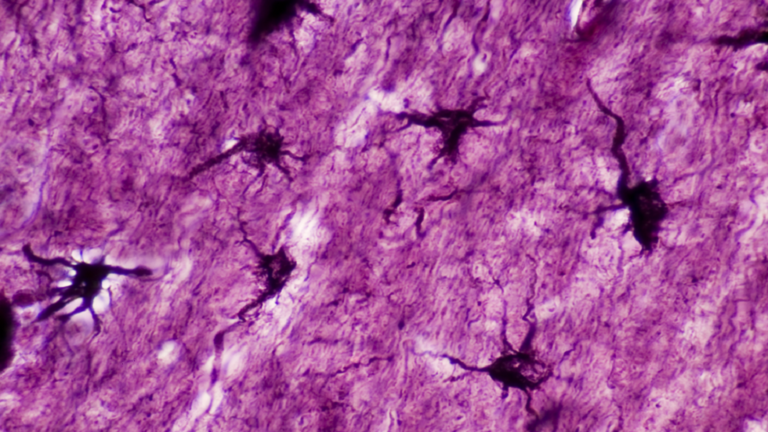

اكتشف فريق دولي من العلماء نوعا جديدا من خلايا الدماغ مختبئا بين الخلايا العصبية والوحدات الداعمة لها.

وكشفت الدراسة أن ما يعرف باسم الخلايا النجمية (الخلايا الداعمة)، تكون وفيرة في الدماغ وتلتف حول الوصلات العصبية مثل “الغراء”. ولسنوات عديدة، افترض علماء الأعصاب أن هذه الخلايا سلبية تماما، وموجودة فقط لحماية الخلايا العصبية.

وبهذا الصدد، عثر باحثون من مؤسسات مختلفة في المملكة المتحدة وأوروبا، على خلية هجينة جذرية في أدمغة الفئران.

وباستخدام تسلسل الحمض النووي الريبي (RNA) لخلية واحدة، حدد الباحثون تسع مجموعات متميزة من الخلايا النجمية المتخصصة في حصين الدماغ. وبرزت المجموعة رقم 7 بشكل مثير للاهتمام، حيث تمركزت في أجزاء منفصلة جدا من حصين الدماغ، مع امتلاك جميع الآليات الجزيئية اللازمة لتعبئة الغلوتامات وإطلاقها.

ووجد الباحثون أن هذه الخلايا المتخصصة تطلق الغلوتامات في نقاط ساخنة دقيقة تشبه المشبك العصبي، الذي يشمل المساحة التي تتواصل فيها خليتين عصبيتين عادة عن طريق إطلاق الغلوتامات.